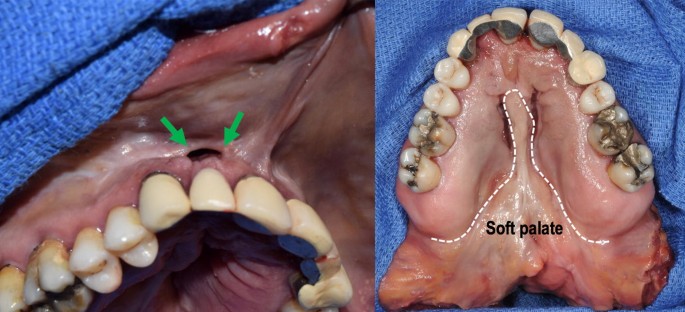

Palate is formed by union of palatal shelves that develop from the maxillary processes and close during 8th or 9th week of gestation. It blends laterally with the palatoglossal and palatopharyngeal arches of the oropharynx. A cleft lip and cleft palate can cause a number of issues, particularly in the first few months after birth, before surgery is done.

Cleft lip and palate deformity is strongly associated with bilateral cleft lips (cls) (86% of cases);

The association decreases to 68% with unilateral cleft lip. Pdf | cleft lip and/or palate (cl/p) is phenotypically diverse, making classification difficult. It blends laterally with the palatoglossal and palatopharyngeal arches of the oropharynx. Learn vocabulary, terms and more with flashcards, games and other study tools.